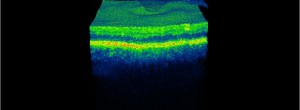

LITE: Desarrollo de Técnicas Avanzadas de Imagen del segmento anterior y posterior del ojo

Reappraisal of geographic atrophy patterns seen on fundus autofluorescence using a latent class analysis approach.